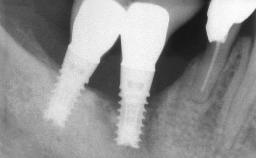

| # of Implants | 4 |

| Type of Implants | One-Piece |

| Attachment | One-Piece |

| Bone Volume | Horizontally and vertically sufficient |